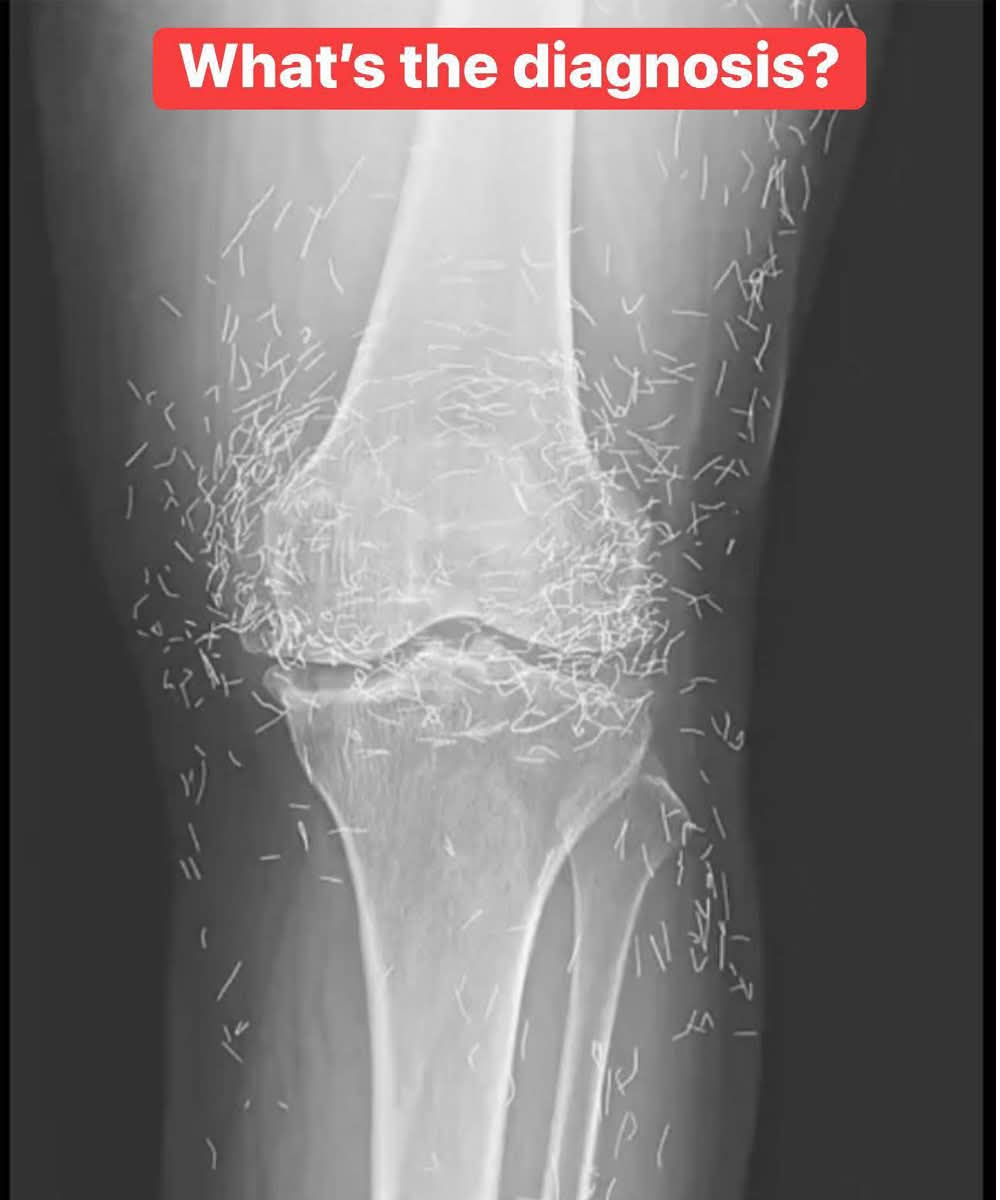

X-Ray Reveals Hundreds of Gold Needles in Woman’s Knees As doctors examined an X-ray image of the knees of an old woman experiencing severe joint pain, they found a gold mine: hundreds of tiny gold acupuncture needles left in her tissue.

The 65-year-old woman from South Korea had previously been diagnosed with osteoarthritis, a condition in which the cartilage and bones within the joints degrade, causing pain and stiffness. However, when pain relievers and anti-inflammatory drugs didn’t alleviate the pain in her knees and only caused stomach discomfort, she had turned to acupuncture, the doctors wrote last week in the New England Journal of Medicine.